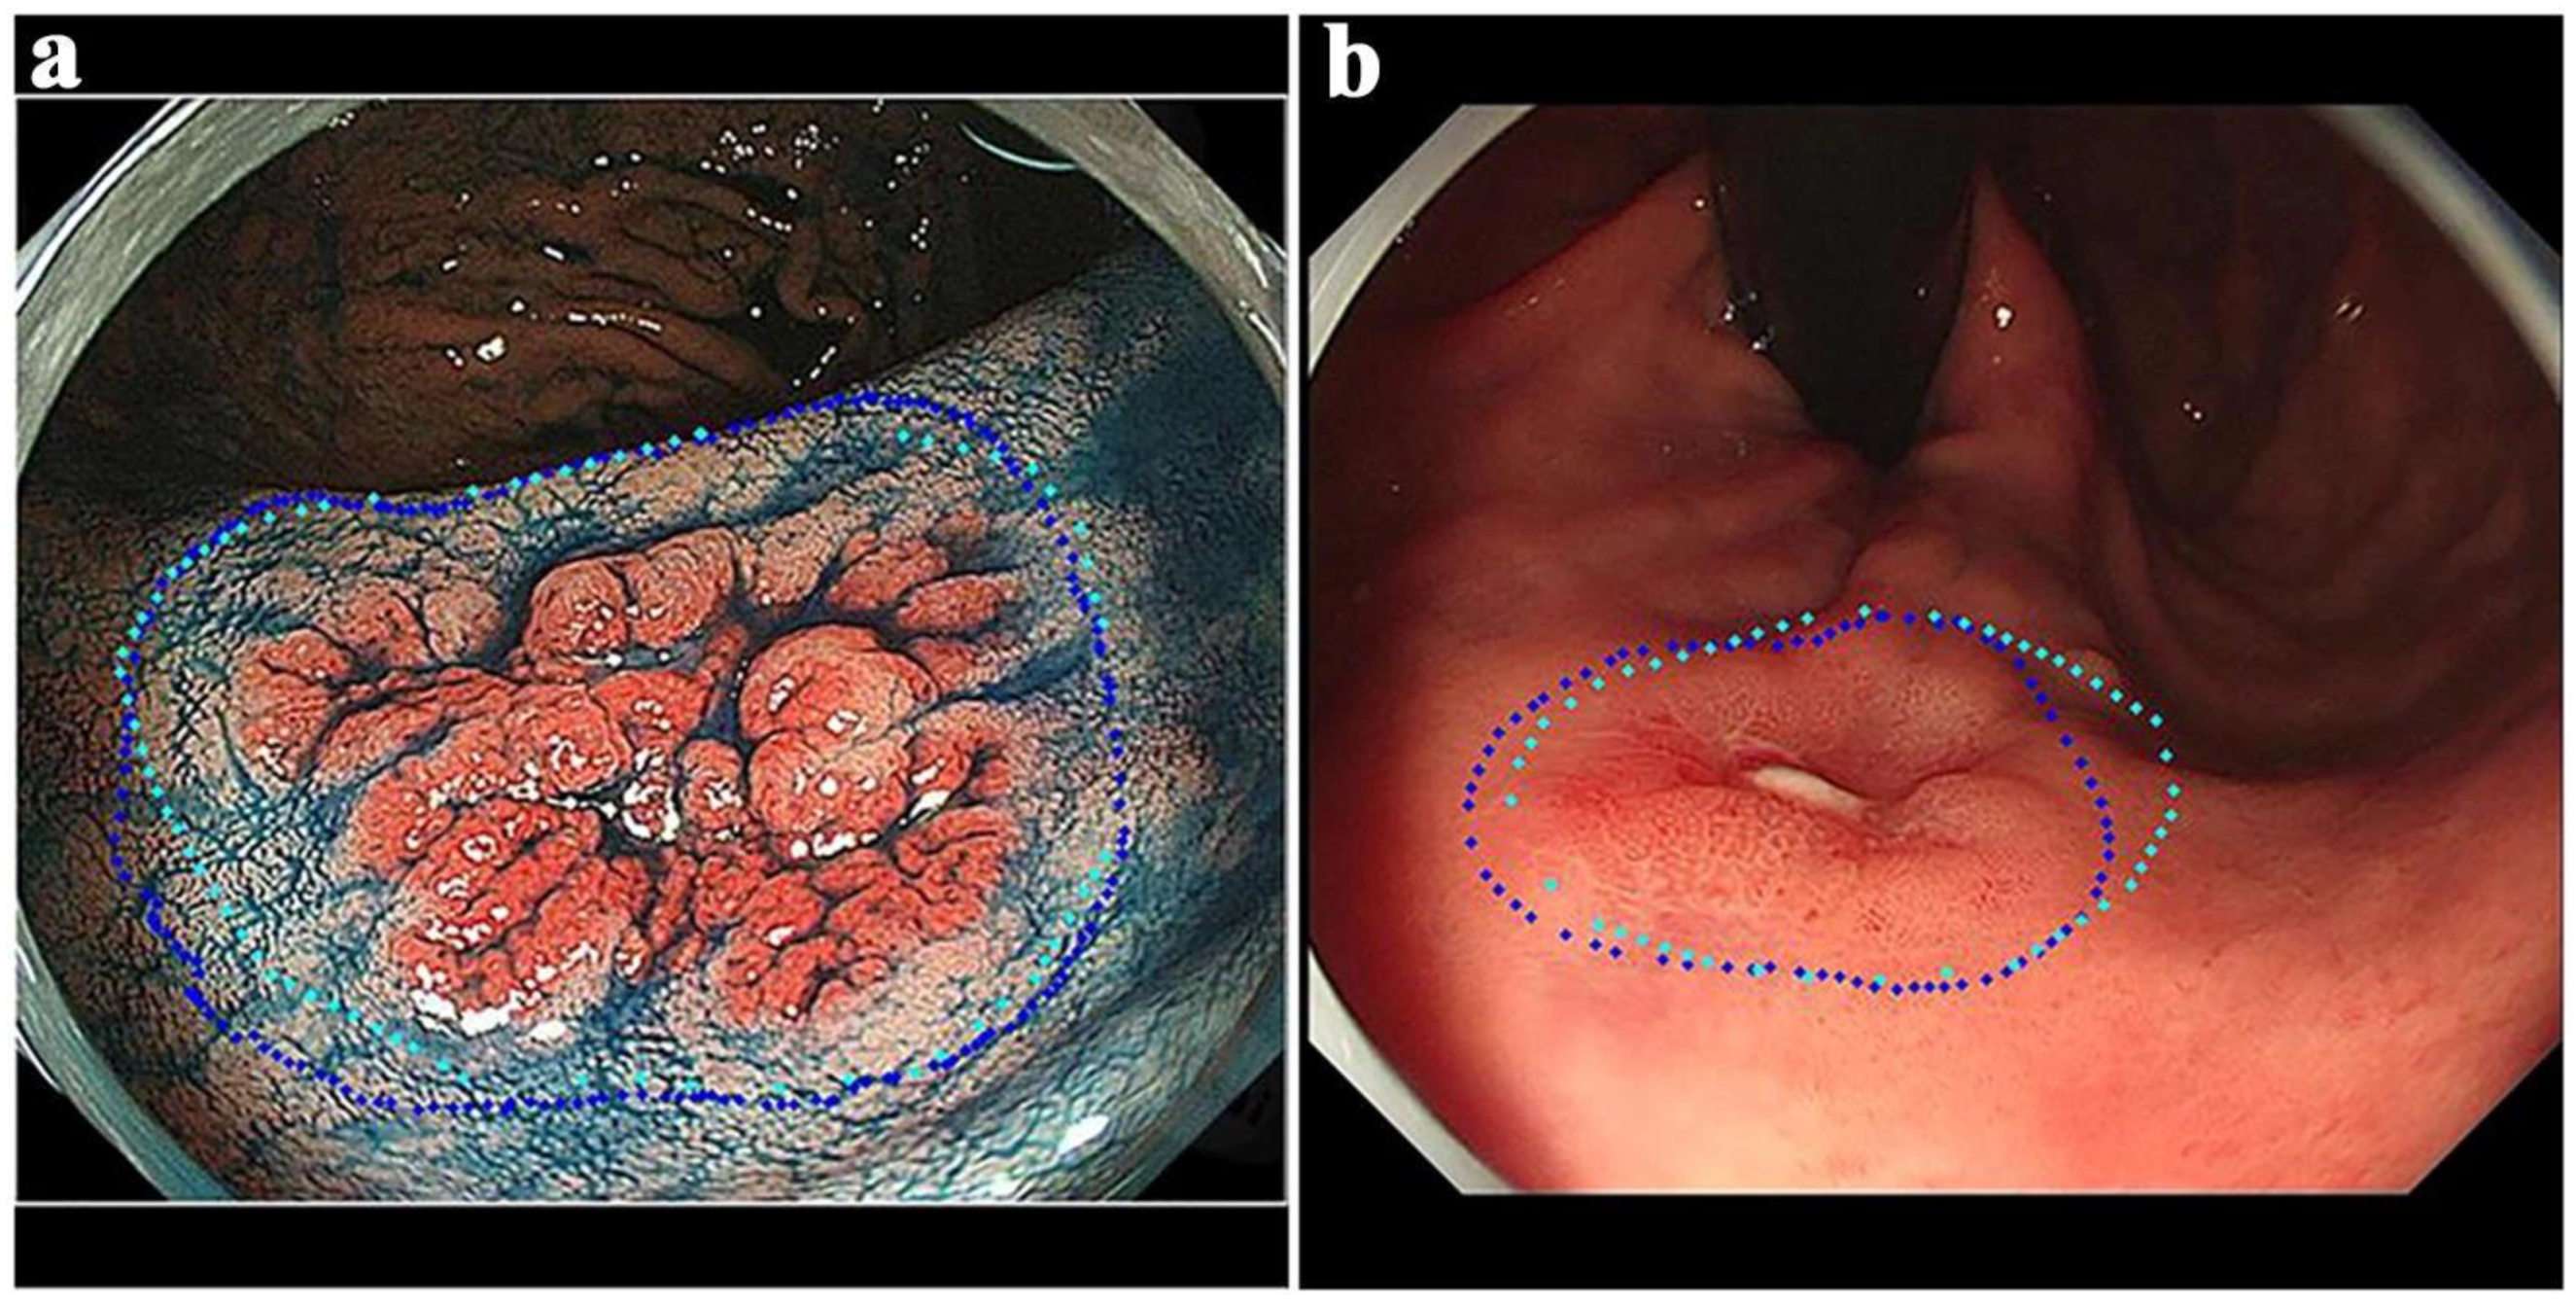

- An, P.; Yang, D.; Wang, J.; Wu, L.; Zhou, J.; Zeng, Z.; Huang, X.; Xiao, Y.; Hu, S.; Chen, Y.; et al. A deep learning method for delineating early gastric cancer resection margin under chromoendoscopy and white light endoscopy. Gastric Cancer 2020, 23, 884–892. [Google Scholar] [CrossRef]